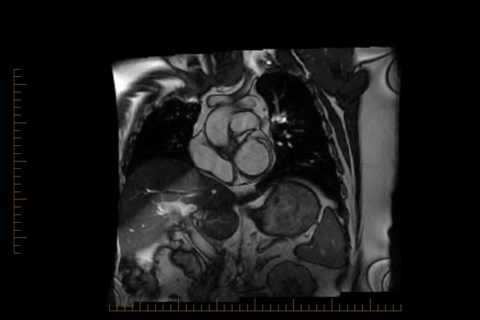

Queensland X-Ray offers cardiothoracic imaging utilising multimodality imaging and interventions for comprehensive investigations of chest, heart, and vascular diseases. Based in Brisbane, fellows will gain a thorough understanding of HRCT of the lungs, oncological imaging, cardiac CT (including coronary angiography, TAVI, and functional imaging), and cardiac MRI. Training includes participation in regular chest and cardiac MDT meetings, and exposure to echocardiography, nuclear medicine cardiac investigations, electrophysiology, and interventional cardiology procedures. Fellows are encouraged to pursue internationally recognised exams for cardiac MRI accreditation.

Our program trains radiologists in advanced cardiothoracic imaging, focusing on the diagnosis of chest, cardiac, and vascular diseases using multimodality imaging techniques. Fellows will gain expertise in HRCT of the lungs, oncological imaging, cardiac CT (including coronary angiography, TAVI, and functional imaging), and cardiac MRI. Training includes exposure to echocardiography, nuclear medicine cardiac investigations, electrophysiology, and interventional cardiology procedures.